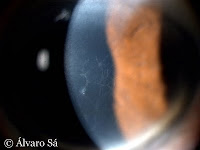

Nas fotografias observamos uma córnea descompensada, com edema do estroma (aumento significativo da espessura corneana). Na segunda fotografia observa-se em pormenor o edema microcístico do epitélio (pequenas vesículas à esquerda do feixe de luz).

Na distrofia endotelial de Fuchs há uma disfunção das células endoteliais (camada mais interna da córnea) responsáveis pela constante desidratação do estroma corneano, permitindo a sua transparência.

Nestas duas fotografias observamos a pigmentação endotelial (camada mais interna da córnea) assim como o aspecto de “metal batido” resultante da confluência das guttae (múltiplos corpúsculos ou pequenas excrescências focais da face posterior da córnea).